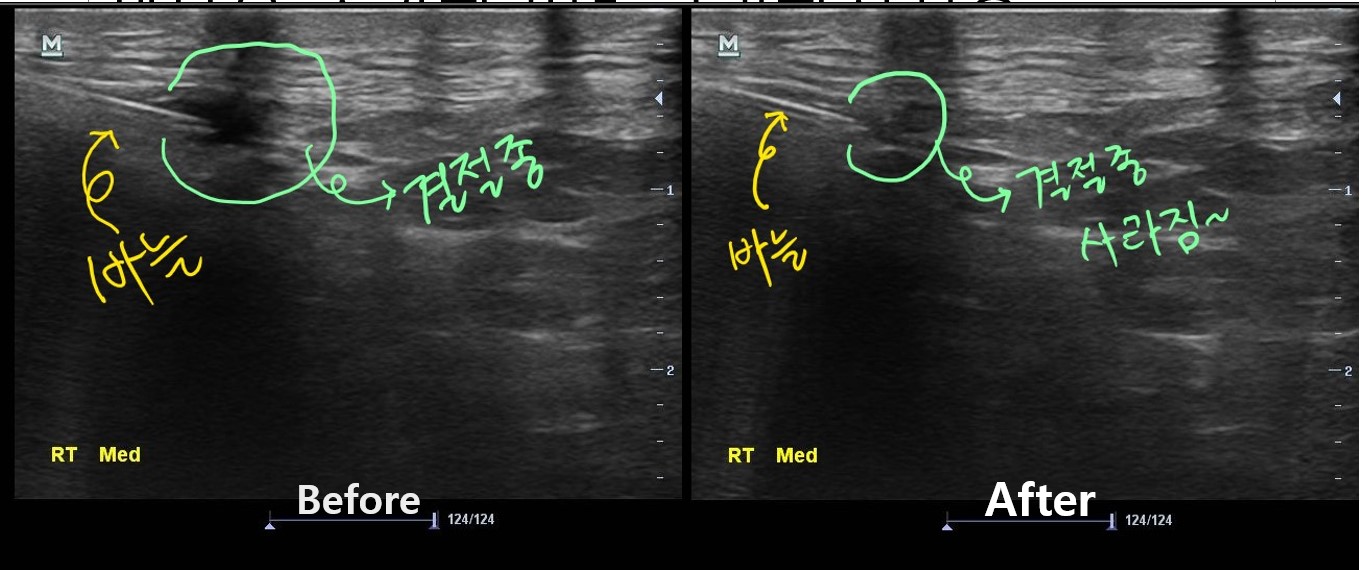

나 : 초음파 보면서 주사기로 물혹속 내용물을 제거해봐야 할거 같습니다.

치료 후 3개월이 지난 현재, 이 환자분은 다행히 물혹이 재발되지 않아 큰 불편함없이 잘 지내고 있습니다. 아직 더 지켜보긴 해야 하지만요...